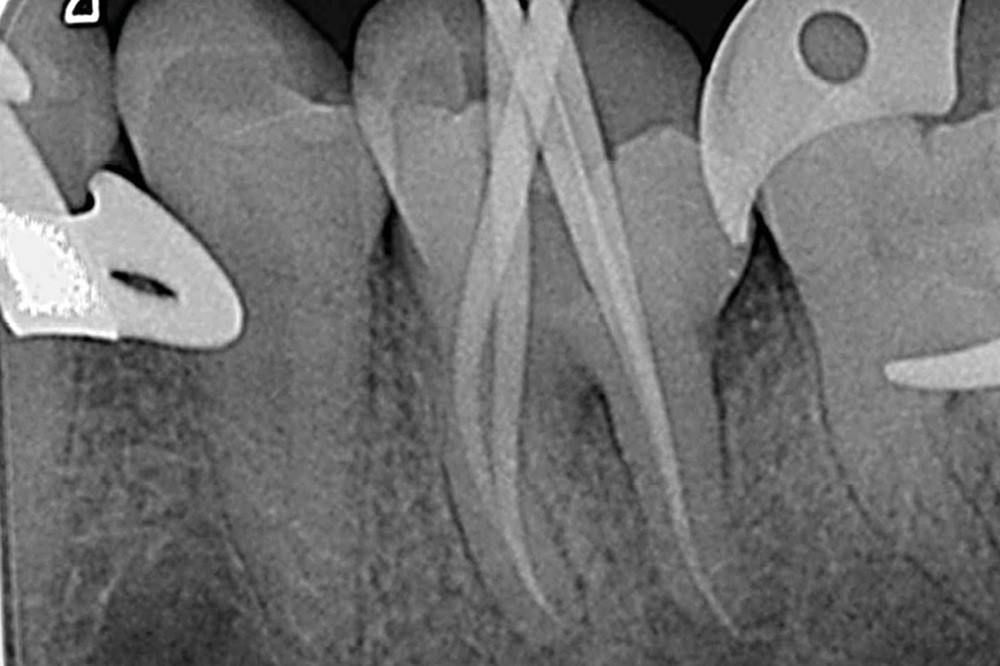

La mise en forme doit également s’adapter aux singularités anatomiques. Pour ce cas clinique, le canal mésio-lingual a été mis en forme en premier jusqu’à la longueur de travail. Puis le test du cône a été réalisé (fig. 4 et 5) afin de voir si les deux canaux se rejoignaient. Ces deux canaux se rejoignant à 3 mm de l’apex, le canal mésio-vestibulaire a été mis en forme à sa longueur de travail moins 3 mm afin d’éviter la zone de confluence et le risque accru de fracturer un instrument. De plus, cette mise en forme longueur de travail-3 mm a son importance pour la précision de l’obturation et l’ajustage des cônes. Pour le canal distal, qui était un canal « en 8 », nous appliquons le même raisonnement que pour les canaux mésiaux, avec un canal principal, test du cône, et ajustage des maîtres-cônes (fig. 6).